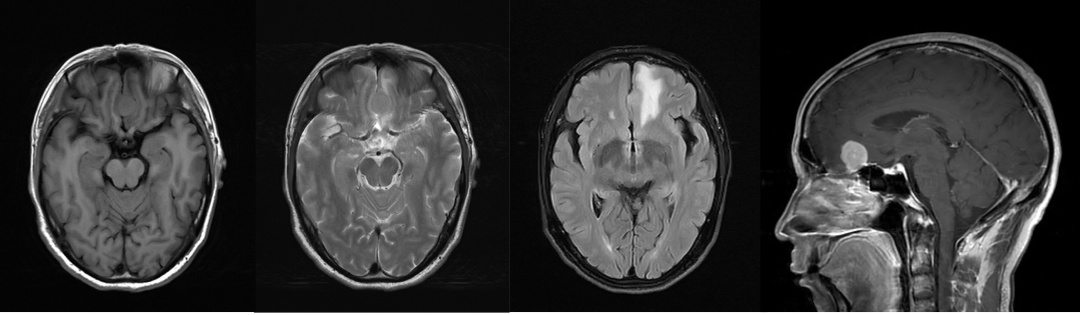

磁共振显示前颅底脑膜瘤

患者老张是一名50多岁的男子,因“近1周反复发作性意识丧失伴肢体抽搐”,于8月2日来到丘北县人民医院神经内科就诊,在完善头颅CT、MRI等相关检查后,他被诊断为“前颅底脑膜瘤”。住院后,县医院立即联系相关科室会诊,华山医院神经外科主治医师岳琪分析患者病情后,建议转入神经外科行手术治疗,与患者家属解释治疗方案及可能的风险后,家属表示充分信任神经外科团队、决定接受开颅肿瘤切除术。